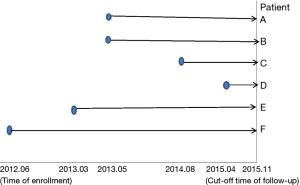

(I) Reasons for non-surgical treatment in the 6 patients were the following: advanced age in one patient (patient A), advanced age and multiple underlying diseases in 4 patients (patient B, C, E and F), and personal unwillingness in one patient (patient D). (II) Time of enrollment was between June 2012 and November 2015, as shown in Figure 3. (III) In the pulmonary lesions treated with 125I radioactive particles, the longest tumor diameter was 6.04 cm, and the shortest diameter was 2.04 cm (3.79±1.37 cm on average). At each site, 20–55 particles were implanted, for a total of 226 particles. One patient received an implantation of 125I radioactive particles twice.

As can be seen from Figure 3, all 6 patients survived. The 5 patients who were followed up for 1 year had a 1-year survival rate of 5/5 (100%), and the 4 patients who were followed up for 2 years had a survival rate of 4/4 (100%). The longest time of follow-up after enrollment was 3 years and 5 months, and the patient still survived.

As shown in Figure 7 and Figure 3, there were 2 CRs and 4 PRs after follow-up for 1 month, indicating a response rate (RR) of 6/6, and a disease control rate (DCR) of 6/6; six patients were followed up for 6 months, including one patient who refused follow-up visit (still alive),while the other 5 patients were followed up regularly, including 3 CRs and 2 PRs; five patients were followed up for 12 months, including 3 CRs, 1 PR and 1 PD, indicating an RR of 4/5, a DCR of 4/5, and a progression rate of 1/5; four patients were followed up for 18 months, including 3 CRs and 1 SD, indicating a RR of 3/4 and a DCR of 4/4; four patients were followed up for 24 months, including 1 patient who refused a follow-up visit (still alive), while the other 3 patients were still followed up regularly; there were still 4 patients who were followed up for 30 months, including 1 patient who refused follow-up visit (alive) and 3 patients who were followed up on a regular basis; one patient was followed up for 36 months and had a recurrence of primary lesion, with the response being evaluated as PD. In addition, Figure 7 shows that patient E achieved significant response after implantation of 125I particles, and the response was evaluated as CR 1 month after implantation (Figures 8,9); however, the primary lesion recurred and was enlarged with left lung metastasis in month 12 (Figures 10,11), whereupon the response was evaluated as PD. The patient was given CT-guided implantation of 125I radioactive particles again for treatment of the recurrent lesion. The repeated pulmonary CT after re-implantation showed significant reduction of tumor (reduction rate 27.32%), as shown in Figure 12, and the response was subsequently re-evaluated as SD.

Other relevant studies have shown a unique advantage of implantation of radioactive particles in the treatment of lung cancer. In a study by Lu et al. (10), 15 patients with obstructive pneumonia caused by central type lung cancer were given a bronchoscopic implantation of 125I radioactive particles, and followed up in months 2, 6, 12, 18 and 24 after implantation. The median survival was 15.6 months, and the one-year lung recruitment rate was 80.0%, which significantly improved the quality of life. To compare, in our study’s response evaluation from regular follow-up of patients who received the CT-guided implantation of radioactive 125I, it was found that the tumors had significantly shrunk in all 6 patients. Typical cases are illustrated in Figures 4 and 5, and as can be seen in Figure 6, the most obvious reduction of tumor was seen in the 6th month of follow-up. In the 5 patients who were followed up, there were 3 CRs, indicating an RR of 5/5 (100%) and a DCR of 5/5 (100%). This shows that the implantation of radioactive particle achieved the best response within 6 months in the treatment of early lung cancer. In addition, as Figure 3 shows, 5 patients were followed up 1 year after implantation and had a survival rate of 5/5 (100%), 4 patients were followed up 2 years after implantation and had a survival rate of 4/4 (100%), and the longest time after enrollment was up to 3 years and 5 months; at the time of writing, this patient is still alive. The observations above demonstrate the significant efficacy of the implantation of 125I radioactive particles in treatment of early lung cancer.